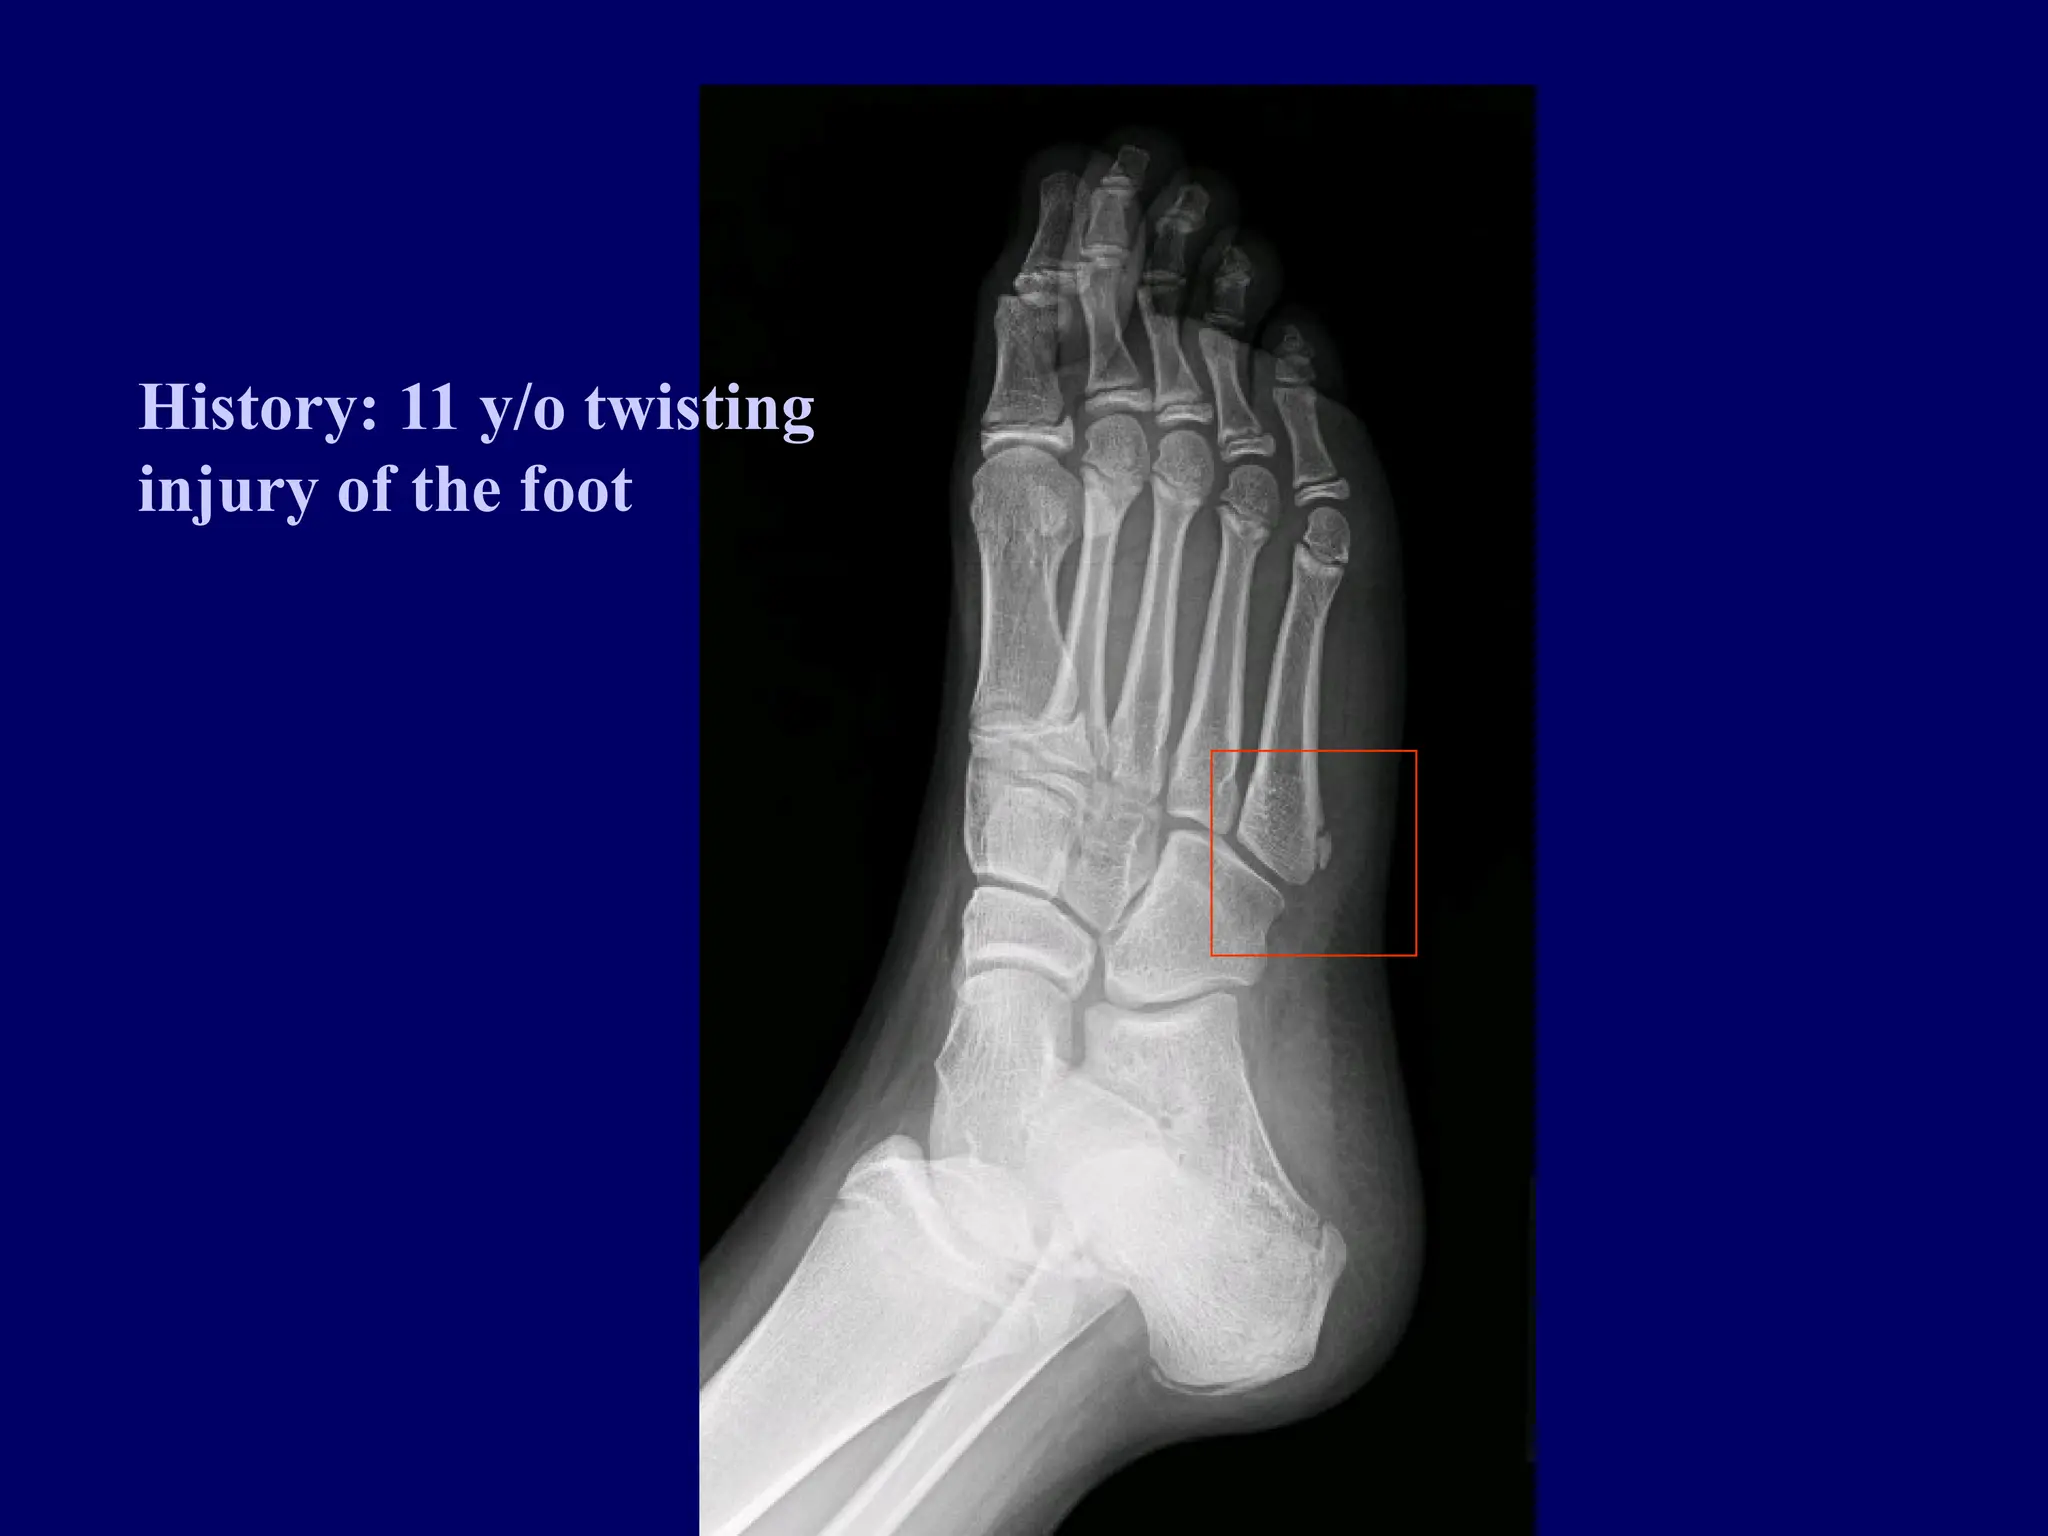

History: 11 y/o twisting

injury of the foot

History: 11 y/otwisting injury of the foot